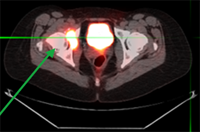

Prior to radiosurgery: painful focus of breast cancer in the right hip with erosion of pelvic bone.

Radiosurgery plan targeting the pelvic tumor and sparing the pelvic organs.

After completion of radiosurgery: complete resolution of pain and the focus of breast cancer in the right hip, with interval healing of pelvic bone (green arrow). Brown arrow points to normal bladder and pelvic organs.